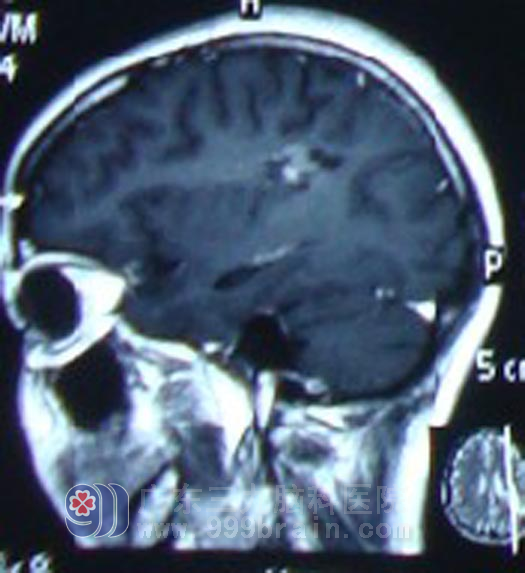

5月6日-6月23日,阿玲转入广东三九脑科医院肿瘤综合治疗中心,接受TMZ100mg同步化疗及适形放疗。放化疗一月后复查头颅MR显示,阿玲的脑肿瘤进一步缩小,继续行巩固性化疗,现在阿玲精神状态良好,恢复了正常生活及工作。

放疗后